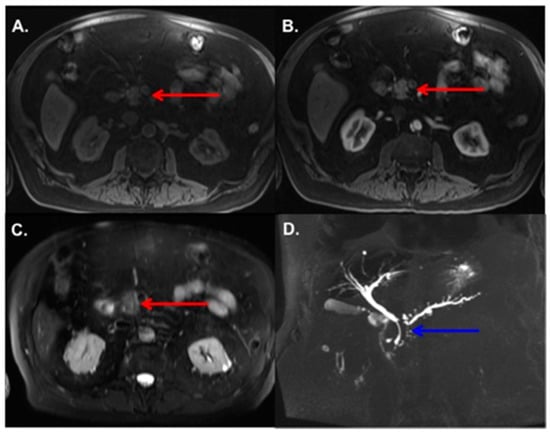

3.2. MRI Findings